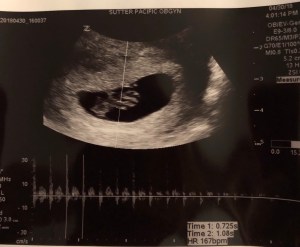

Your Daddy and I don’t know much about you yet, but we know you have a strong heartbeat, you’re 16 weeks along, and you have quite a large head! And even though we don’t know much about you, we already love you so much. And we can’t wait to meet you on (or around) December 9th, 2018.

The first couple months of your life were exciting but admittedly hard. Not because of the morning sickness, but the lack thereof. I heard stories from friends and the blogosphere that nausea, fatigue, frequent urination, acne, mood swings, food aversions/cravings, etc. were typical in the first three months. And I had some of that, but not a lot. I threw up on the bus to work once, sometimes I’d feel nauseous in the morning, and I couldn’t even look at spinach, but that was about it. Without daily pregnancy symptoms, I kept wondering if you were still growing and healthy. How could we know? We couldn’t. We had to wait 29 agonizing days for our first ultrasound — which Daddy calls Baby Facetime — and it was the most beautiful and special day ever. We got to see you, hear your heartbeat and confirm that everything was just fine! Phew!!